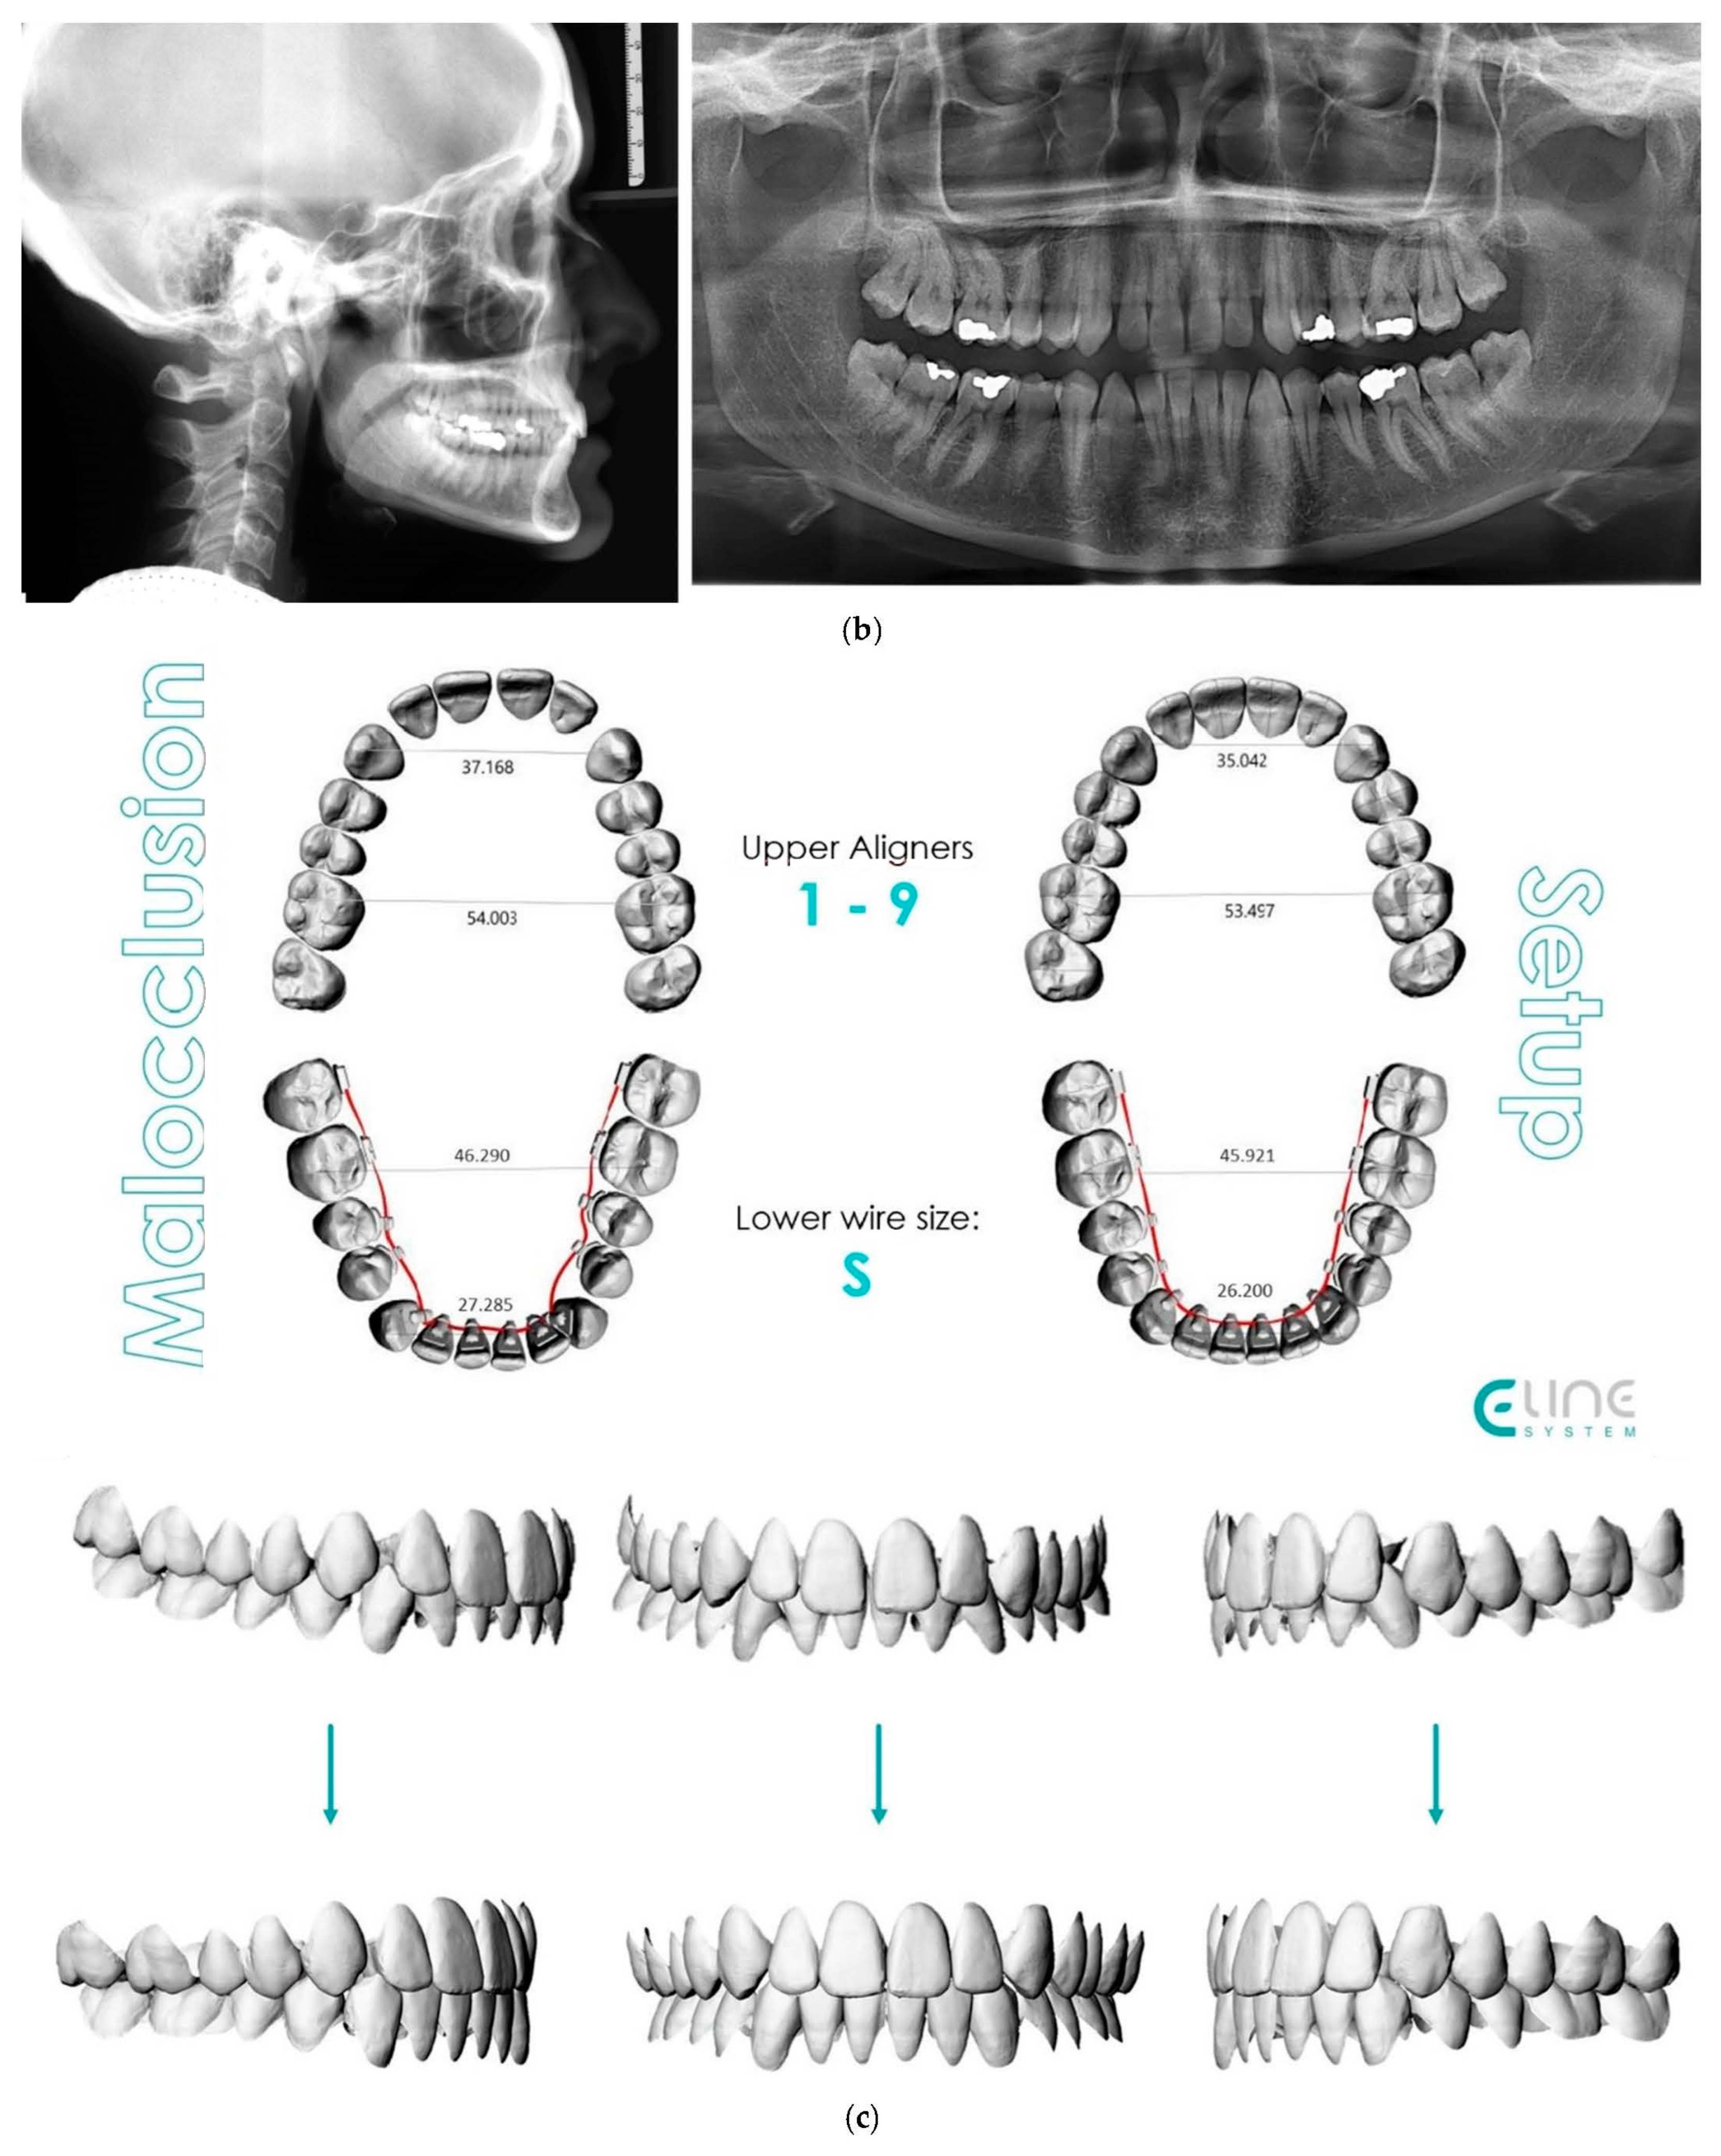

4.3. Case 3: Class II Subdivision with a Deep Bite